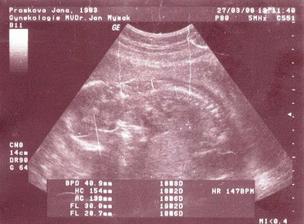

10.3. Velký UTZ dopadl dobře, miminko je prý v pořádku, ale velikostně jsme o týden mladší, tak nebylo vidět úplně všechno, tak jdeme za 14 dní znovu. Miminko se hrozně mlelo, tak nevíme zatím ani pohlaví, ale snad to bude už za těch 14 dní vidět. Takže 27.3. další velký UTZ :o)

27.3. UTZ dopadl dobře, máme vše , co máme mít a nikde nic nepřebývá... ale hrášek byl schoulenej, takže pohlaví zatím nevíme...